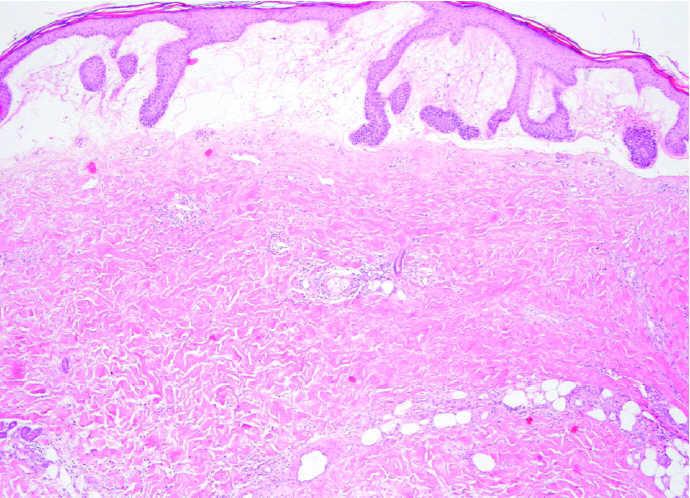

Fig. 4.--Biopsia de ampolla. Ampolla subepidérmica a expensas de marcado edema de dermis papilar; haces colágenos compactos y engrosados. (Hematoxilina-eosina, ×40.)

En la biopsia de la ampolla (fig. 4), hay un marcado edema de la dermis papilar que da lugar a la formación de una ampolla subepidérmica. En la dermis subyacente se observan infiltrados perivasculares e intersticiales constituidos por linfocitos y eosinófilos. En la dermis superficial se encuentran haces colágenos compactos y engrosados, sin objetivarse alteraciones de las fibras elásticas. No hay dilatación de vasos linfáticos. El estudio de inmunofluorescencia directa con los antisueros anti-IgG, anti-IgA, anti-IgM y anti-C3, fue negativo.